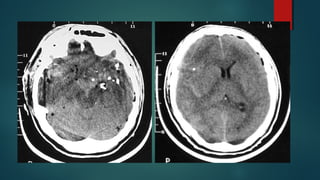

Este documento es el programa para un taller de imágenes del curso de emergencia 2015 impartido por el Dr. Víctor Delgado. El taller se centra en el uso de imágenes médicas para el diagnóstico y tratamiento de pacientes en coma traumático según la base de datos de Marshall. El Dr. Delgado es el único instructor repetido a lo largo del documento.